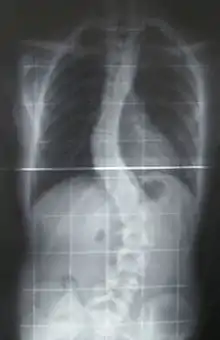

The prognosis of this sub-type of MD indicates that the affected individual may eventually have feeding difficulties. Surgery, at some point, might be an option for scoliosis.[3]

Scoliosis, which is a sideways curve of the persons vertebrate, is determined by a variety of factors, including the degree (mild or severe), in which case if possible a brace might be used by the individual.[14]